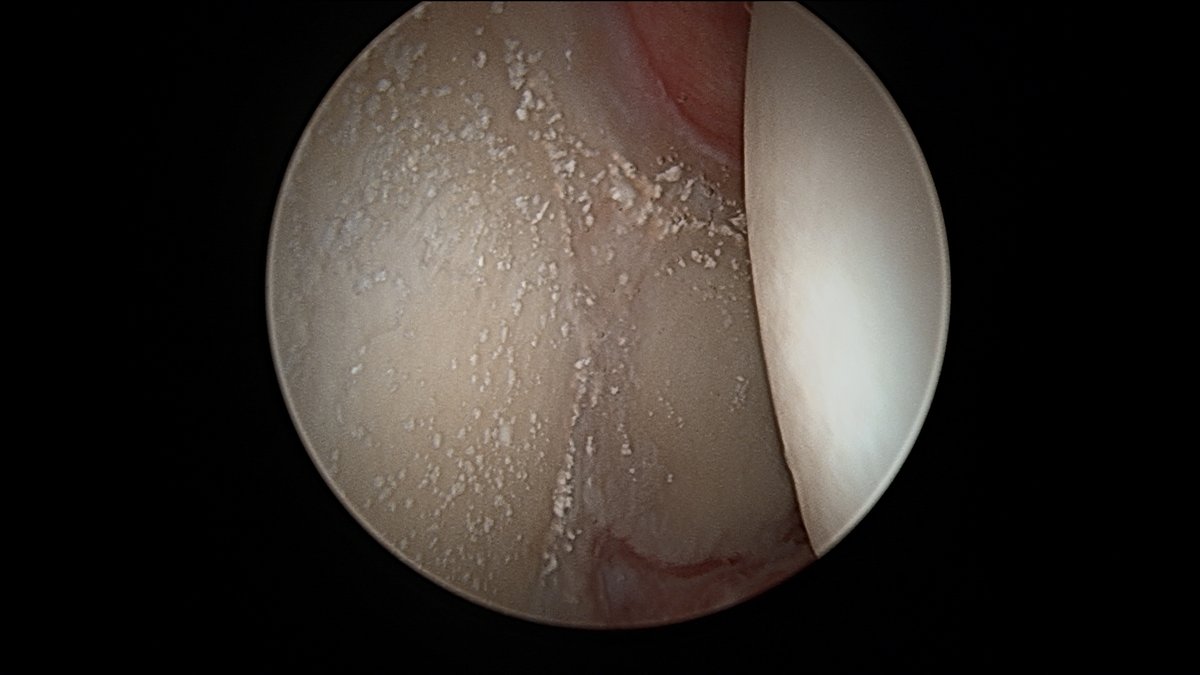

This is chondrocalcinosis isn’t it - not corticosteroid related ? 🤔

This is what a couple previous cortisone injections will look like during #hip #arthroscopy Interesting only on acetabulum, not on femoral head. Do you think these "crystals" (which, by the way, are almost impossible to get out without removing the cartilage) are a problem?